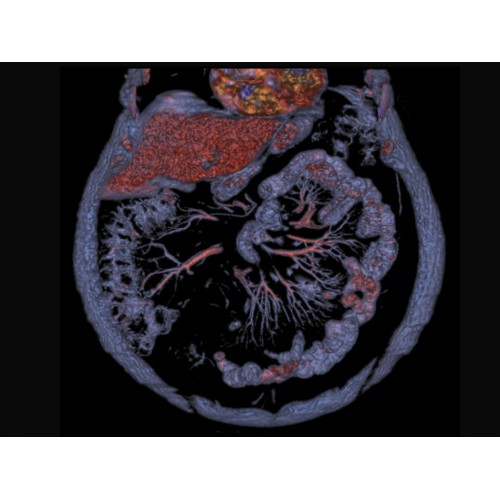

Современный КТ аппарат GE Optima CT520 – это инновационное оборудование для точной и быстрой диагностики. Он сочетает в себе передовые технологии, надежность и удобство использования, что делает его востребованным в медицинских учреждениях различного профиля.

• Высокое качество изображения благодаря усовершенствованной системе реконструкции данных.

• Широкая область применения: от неврологии до кардиологии и онкологии.

КТ аппарат GE Optima CT520 используется для диагностики широкого спектра заболеваний:

Онкология

• Раннее выявление новообразований и контроль эффективности лечения.

• Планирование лучевой терапии с высокой точностью.